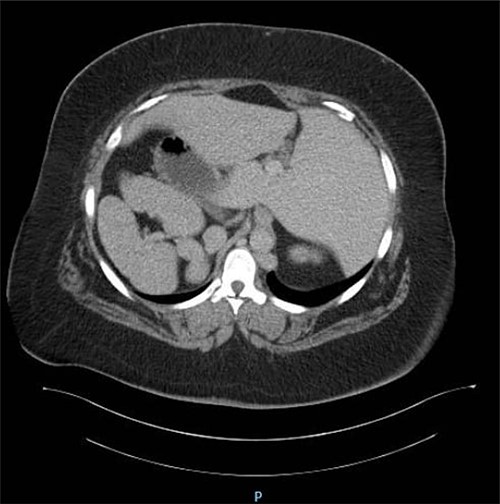

The patient underwent complete preoperative workup which includes clinical history, physical examination, complete blood count (CBC), coagulation profile, chemistry, lipid profile, endocrinology tests, US abdomen, chest X-ray, transthoracic echocardiography, computed tomography (CT) chest and CT abdomen, which showed reversal of intra-abdominal organs as shown in Figs 1, 2 and 3.

CT abdomen showing reversal of intra-abdominal organs with polysplenia.